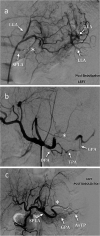

Fig. 2

Types of PSAE. a Type I, AVP (white star) was deployed proximally to the DPA, note perfusion of the spleen via prominent LGA collateral circulation. b Type II, AVP (white star) inserted between DPA and GPA origin, spleen perfusion via collateral pancreatic circulation. c Type III, coiling (white star) distal to GPA, minimal splenic perfusion via AsTP